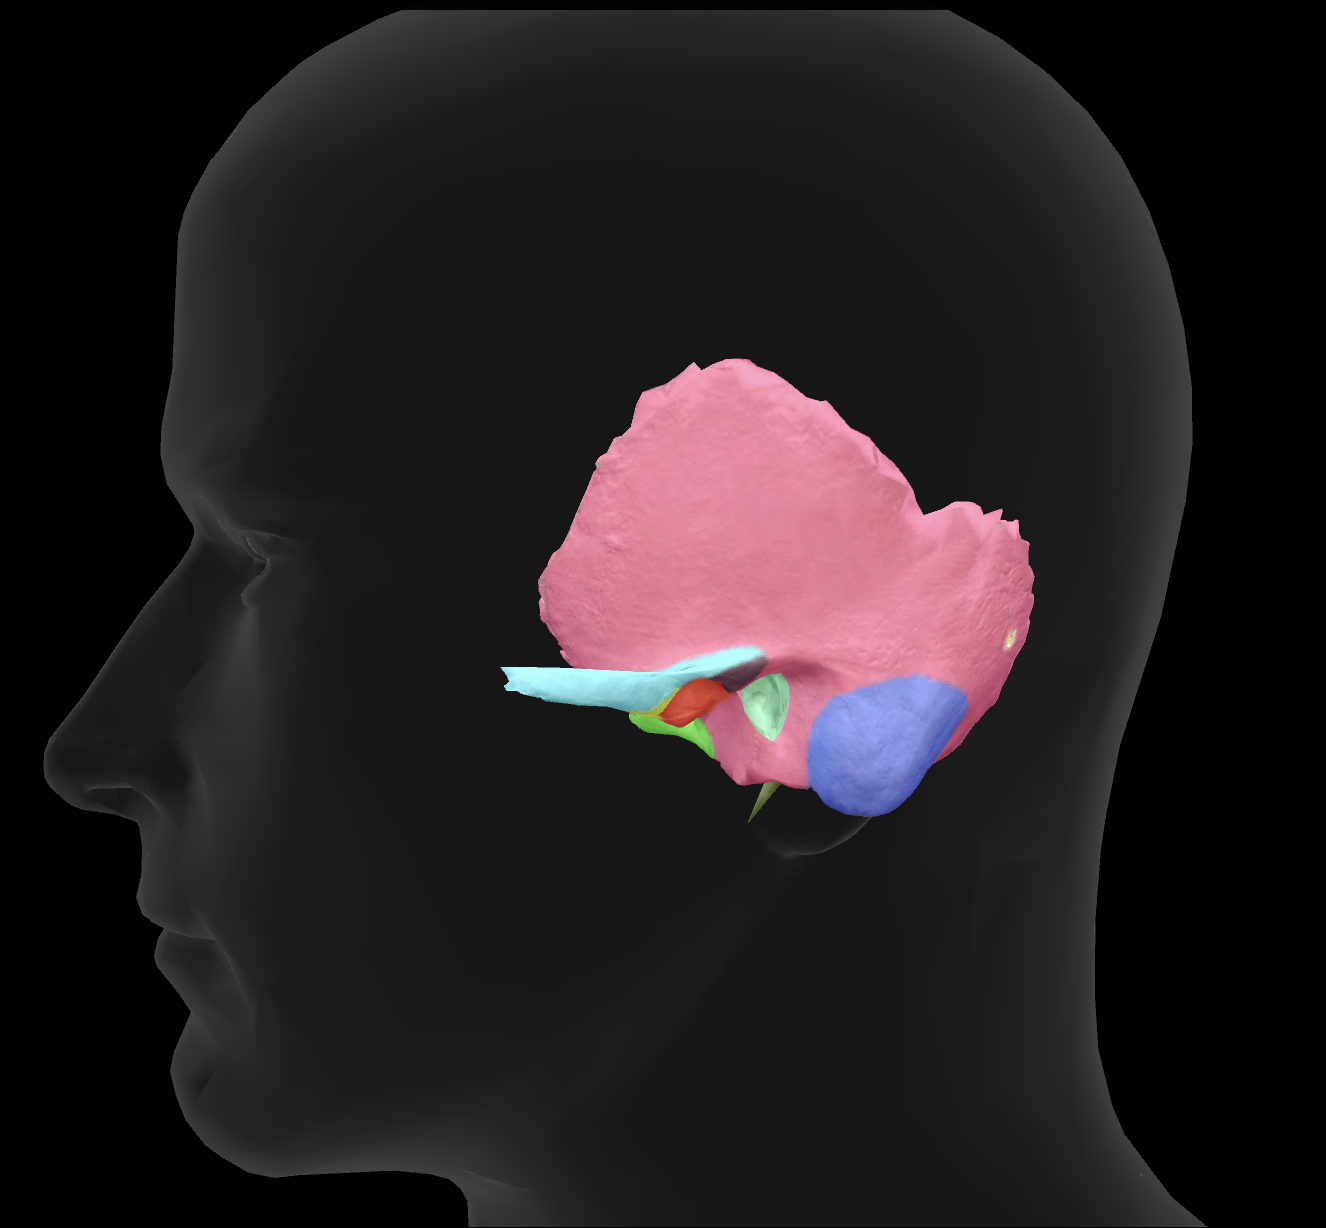

What bone is highlighted?

zygomatic bone

zygomatic process of temporal bone

What is the name of this feature?

external auditory meatus

What is the name of this feature?

mandibular fossa

What is the name of this feature?

mastoid process

What is the name of this feature?

styloid process

What connects to the zygomatic process to make the zygomatic arch?

temporal process of the zygomatic bone